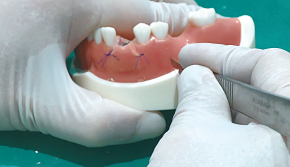

3. Bone Carrier로 골이식재 수집

-

4. Bone Carrier를 터널 공간에 삽입